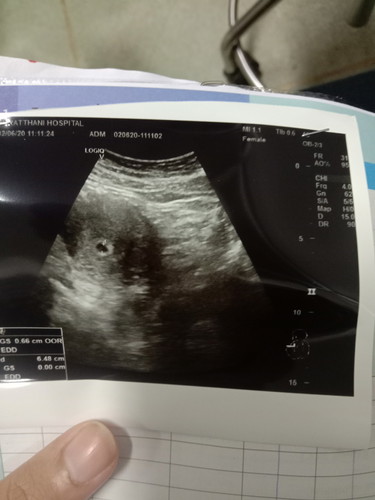

ปจด.ขาดไป2เดือน ไปตรวจที่รพ. ผลคือตั้งท้องอ่อนๆ ผ่านไป 2อาทิตย์ ไปฝากครรภ์ที่รพ. แต่หมอซาวเจอแต่ถุงตั้งครรภ์เล็กๆ ไม่เจอเด็ก ยังงี้ท้องลมรึป่าวคะ

กี่วีคแล้วคะ จะเจอน้องช่วง8w ค่ะ